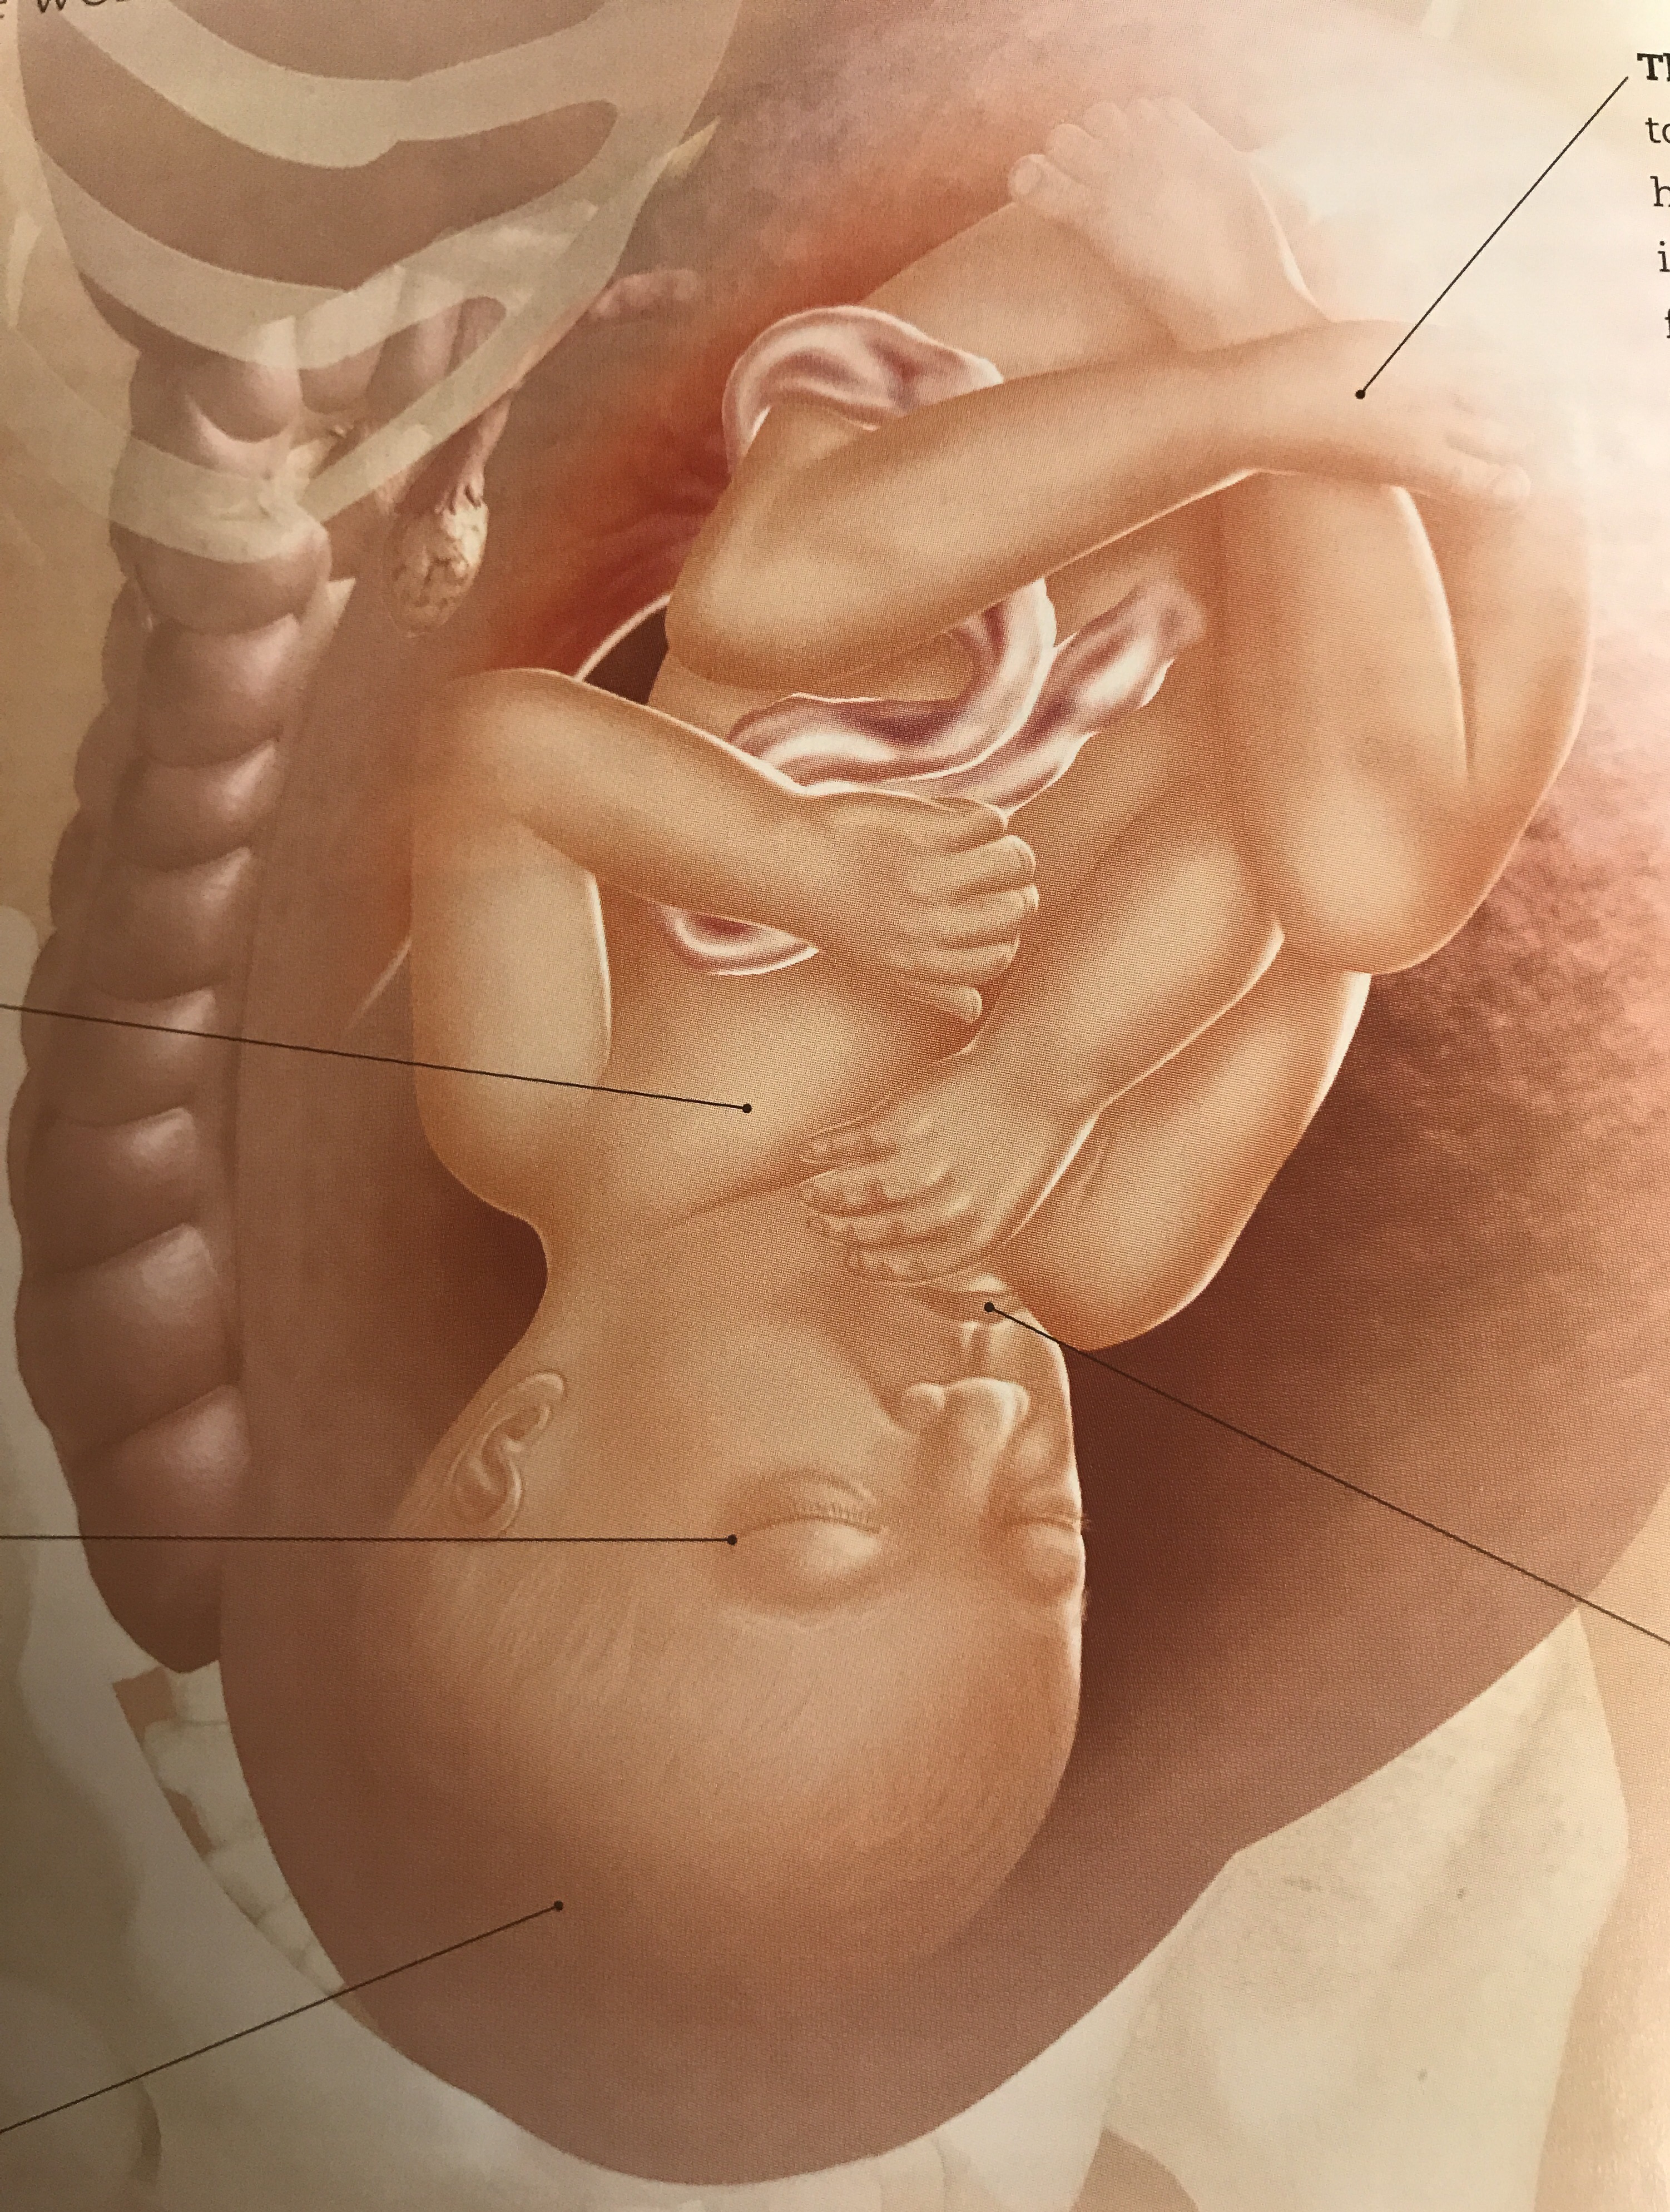

This week our baby’s central nervous system matures even more as do his or her lungs. His or her skin will smooth out, and additionally fat layers which help regulated internal body temperature are getting larger.

The placenta will not get any bigger at this point. As I’ve noted before Gestational Diabetes fasting numbers may be a little harder to control in the next two weeks, and in fact, I did have to up my Insulin units last night, though, at week 36 and beyond they tend to stabilize.